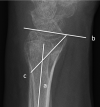

Background Displaced distal radius fractures are prone to redisplacement after manipulation. This can result in the need for delayed surgery. Several criteria have been studied to predict the likelihood of redisplacement. We hypothesized that reduction in the volar cortex would be an additional predictive factor. Purpose The aim of this study was to assess whether the quality of the volar cortex reduction predicts the subsequent need for further intervention (surgery or remanipulation). As a secondary outcome, we assessed whether the quality of the reduction predicts the rate of malunion. Methods A retrospective review was performed of displaced adult distal radius fractures over a 2-year period that had undergone closed reduction at presentation. We identified 105 patients and a review of their electronic notes and radiographs was then performed. The volar cortex reduction was defined as "anatomical," "opposed," or "displaced." We assessed the radial height, radial inclination, radial/ulnar translation, volar/dorsal angulation, teardrop angle, presence of dorsal comminution, quality of the cast (molding, cast index), and volar cortex reduction. These measurements were taken at five time points (prereduction, postreduction, 1 week, 2 weeks, and 6 weeks). All patients that subsequently required surgical fixation or repeat reduction were identified as the primary outcome measure. The 6-week radiographs were assessed for radiographic malunion as our secondary outcome measure. A statistical analysis was then performed to assess the factors that influenced a loss of position and the need for delayed surgical intervention. Results Of the 105 patients, 22 patients required delayed surgery, 3 patients underwent a repeat manipulation, and 12 patients had a radiographic malunion at 6 weeks. During the study period, the proportion of patients requiring surgery or repeat manipulation in the displaced group was 10/21 (47.6%), in the opposed group it was 11/50 (23.4%), and in the anatomic group it was 4/36 (11.1%; p = 0.008). We then included the patients with a radiographic malunion and found the proportion of patients with an adverse outcome in the displaced group was 14/21 (66.7%), in the opposed group it was 17/47 (36.2%), and in the anatomic group it was 6/36 (16.7%; p = 0.001). At the 1-week time point, this association was equally significant, as the proportion in the displaced group was 17/33 (51.5%), in the opposed group it was 15/45 (33.3%) and in the anatomic group it was 1/22 (4.5%; p = 0.001). The patients' age, quality of cast, presence of dorsal comminution, and degree of initial displacement did not predict the subsequent need for surgery or remanipulation. Conclusion The most important factor in our study for significant redisplacement of an initially dorsally displaced distal radius fracture is the association of the volar cortex. This parameter maintains significance at the 1-week time point. This data shows that volar cortex reduction is a useful clinical measurement in assessing which distal radius fractures will undergo delayed displacement requiring intervention. Level of evidence Level 3-Retrospective comparative study.

Figures